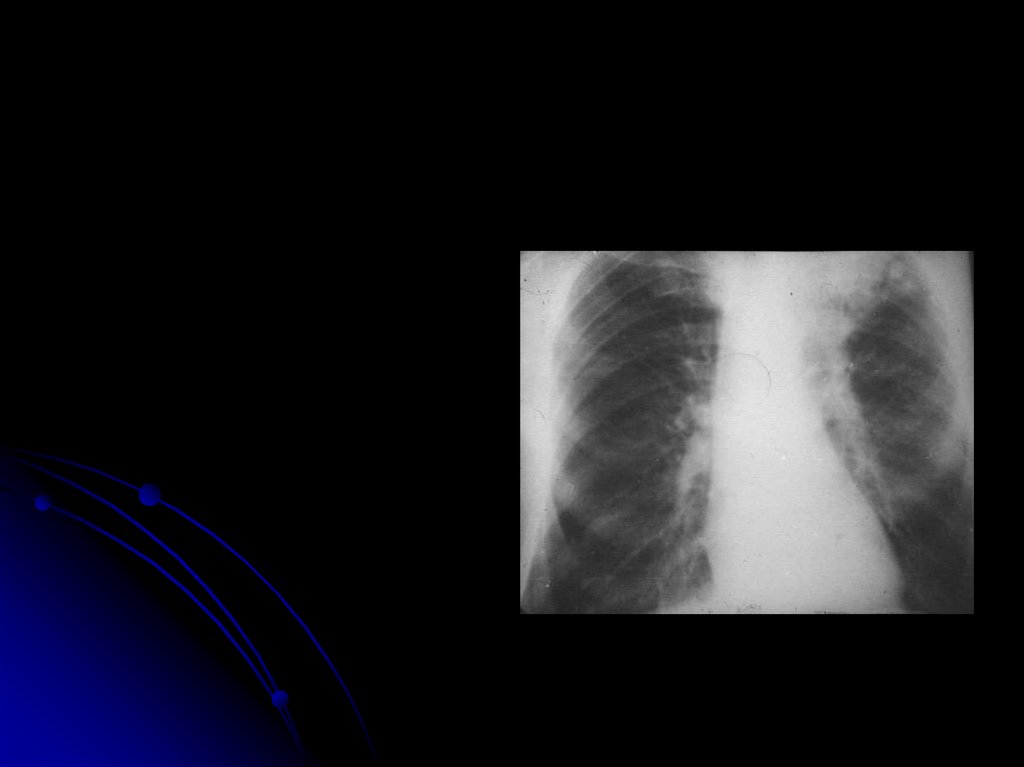

Начальная стадия – до прорыва

Начальная стадия-до прорыва

7. Начальная стадия-до прорыва